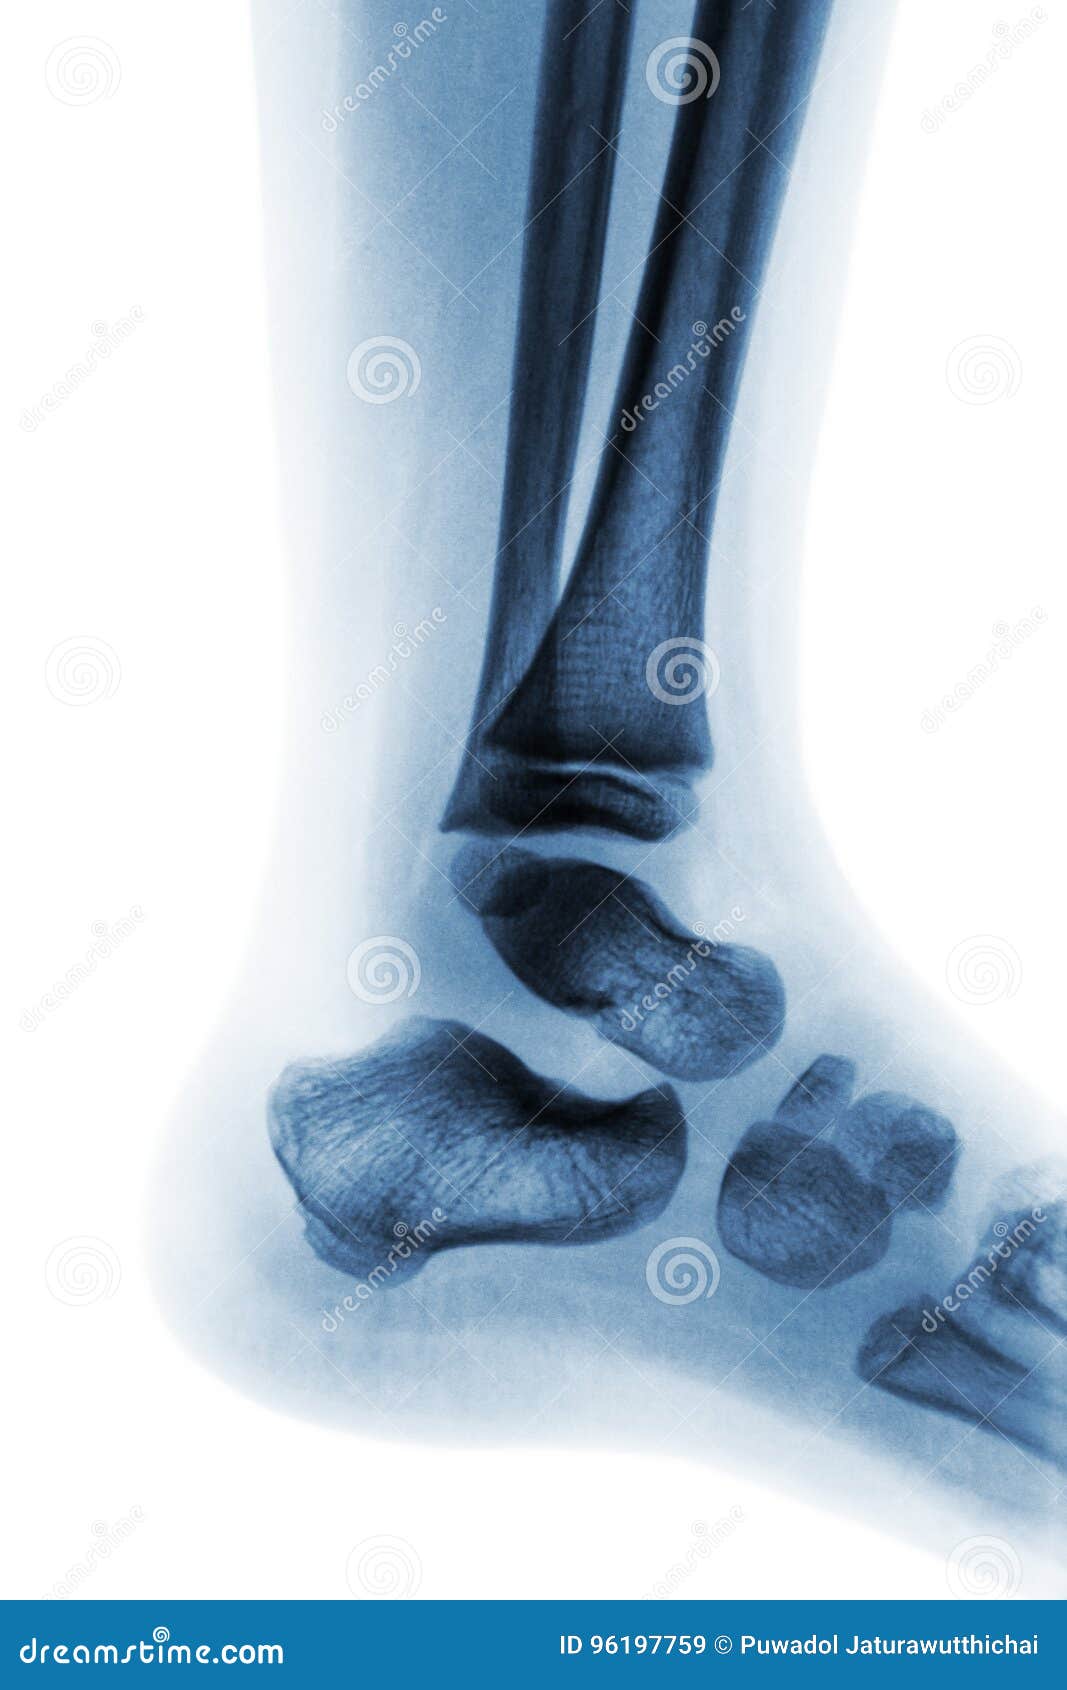

From www.dreamstime.com

Film Xray of Normal Child Ankle . Lateral View Stock Image Image of newborn, medicine 96197759 Child Ankle Xray Normal this is a repository of normal pediatric bone xrays and their examples for a quick reference look. See the annotated images below from wikifoundry, and thanks also to radiopaedia: It should be noted, though, that in some countries, including the uk, only the mortise and lateral are used. ottawa ankle rules: Bony fragment at the tip of medial. Child Ankle Xray Normal.

Film Xray of Child S Foot ( Side View ) ( Lateral ) Stock Image Image of heel, lateral 58744591 Child Ankle Xray Normal ankle radiographs are frequently performed in emergency departments, usually, after trauma, the. this is a repository of normal pediatric bone xrays and their examples for a quick reference look. Xrs are indicated if any of the following criteria are met. See the annotated images below from wikifoundry, and thanks also to radiopaedia: ottawa ankle rules: It should. Child Ankle Xray Normal.